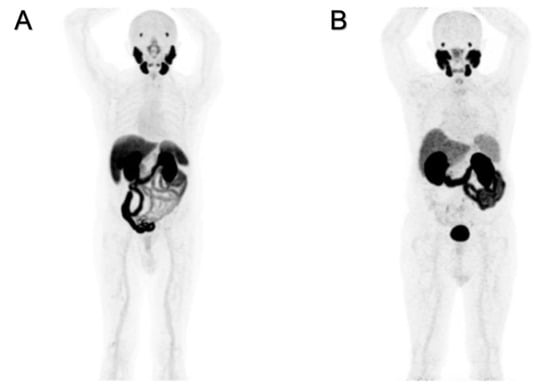

[18F]PSMA-1007 and [68Ga]Ga-PSMA-11 have different patterns of uptake in normal organs, as shown in Figure 1A,B. The “physiological”, hepatic, uptake is higher for [18F]PSMA-1007 than for [68Ga]Ga-PSMA-11. Increased hepatic extraction of [18F]PSMA-1007 causes increased excretion throughout the intestine, and often prolonged retention within the gall bladder is observed. This finding is related to the higher lipophilicity of fluorinated radioligand. Such biodistribution might interfere with the detection of the involved abdominal lymph nodes.

Increased uptake and elevated excretion via the urinary system are prevalent for [68Ga]Ga-PSMA-11. The prolonged and persistent presence of radioactive urine in the bladder might musk recurrences in the prostate and/or pelvic lymph nodes.

At least two significant differences were detectable on PET images and were strictly related to the pharmacokinetic properties of these two radioligands as shown in Figure 2. A greater physiological hepatic retention occurs when using [18F]PSMA-1007, and it is related to the highest lipophilicity [14,15]. In kidneys and the urinary tract, [68Ga]Ga-PSMA-11 accumulates highly because of its greater hydrophilicity. Among the differences between the two radiopharmaceuticals, a greater [18F]PSMA-1007 uptake in the skeleton is frequently observed, which according to the extensive and prolonged quality controls we have performed in our experience, is not related to free [18F]Fluorine. The nature of the isotope may be a possible explanation: the lower positron energy and the higher rate of photon emission (photon flux density) of [18F]Fluorine compared to [68Ga]Gallium contribute to the detection of more positive benign lesions in the skeleton, related to increased osteoblastic activity (i.e., osteoarthritis, degenerative changes, fractures, etc.) [16,17].

Figure 2. Negative PET/CT scans: patient (A) was examined with [18F]PSMA-1007, and patient (B) was examined with [68Ga]Ga-PSMA-11.